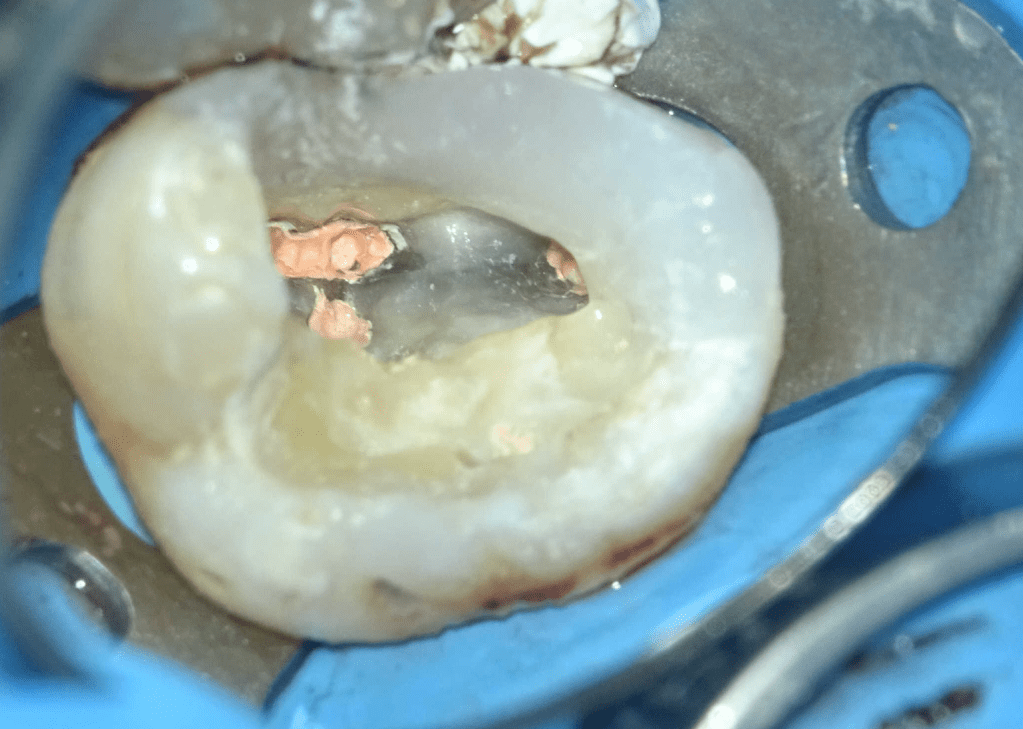

Fisura, remoción amalgama para explorar